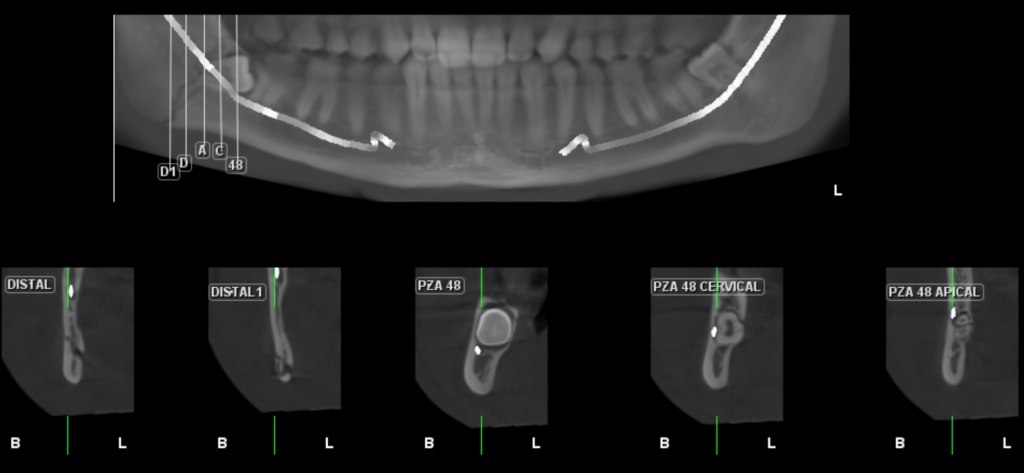

A la evaluación de la tomografía volumétrica (CBCT) en los cortes tangenciales (Figura 2) y transaxiales (Figura 3), se aprecia imagen línea de fractura desde cima de reborde alveolar en zona retromolar derecha hasta zona anterior del ángulo mandibular, así mismo, se observa ligera separación de segmentos óseos desde la zona apical de pieza 48 hasta la basal mandibular, comprometiendo conducto

dentario inferior

CORTES TANGENCIALES

CORTES TRANSAXIALES